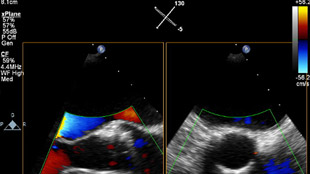

تم تشخيص أحد المرضى لديك بتضيّق في الصمام الأورطي المصحوب بأعراض. يبلغ عمر المريضة 85 عامًا وهي تعاني من السكري وارتفاع ضغط الدم. أنت تدرك خطورة وضعها الصحي ما يجعلها غير مناسبة لجراحة القلب ولكن يسمح لها بأن تكون مرشحة لاستبدال الصمام الأورطي باستخدام القسطرة (TAVR). في يومنا هذا، تمنح حلول التصوير المبتكرة والأجهزة التي تعمل عن طريق الجلد الأمل لبعض المرضى الذين لا تتوفر لهم حتى الآن أي خيارات علاجية أخرى.